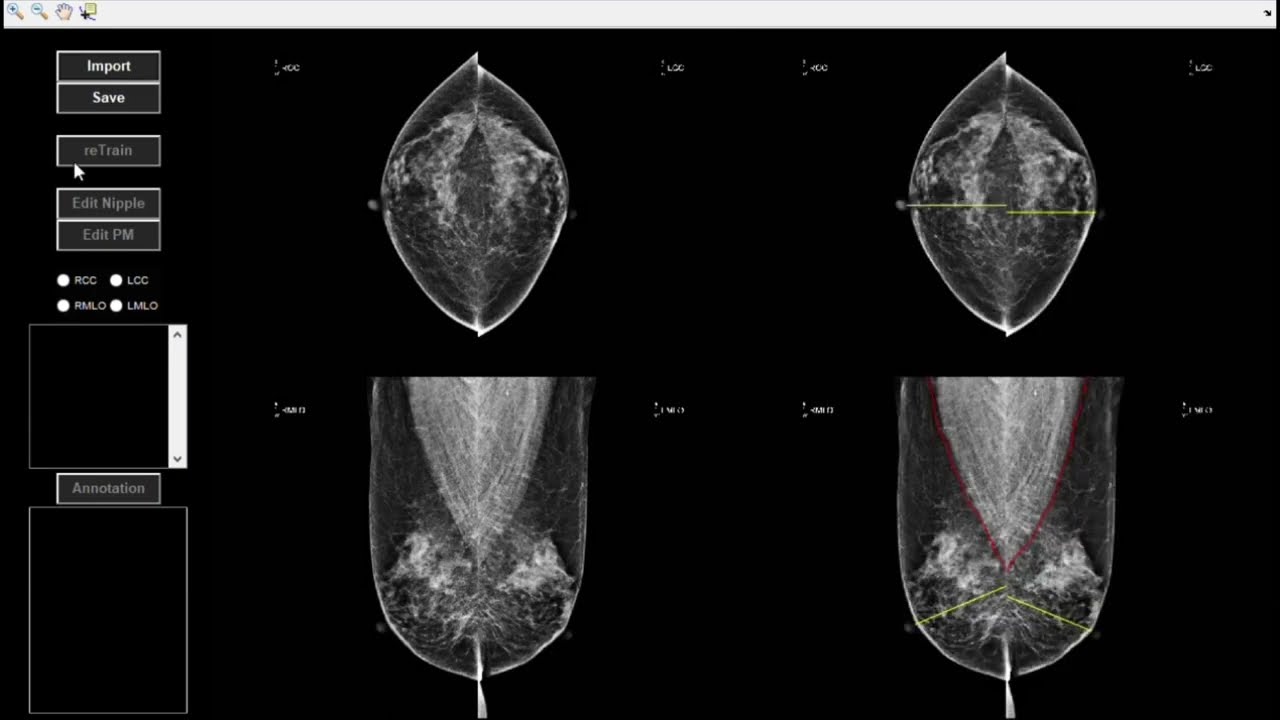

Mammography Quality Evaluation (MQE) uses 11 criteria of mammography quality that enhance radiographers’ skills and mammography process. Radiographers can adjust operations referring to MQE’s quality warnings and visual information. MQE helps hospitals to acquire quality mammograms and minimizes the chance of patient recall for retaking mammograms.